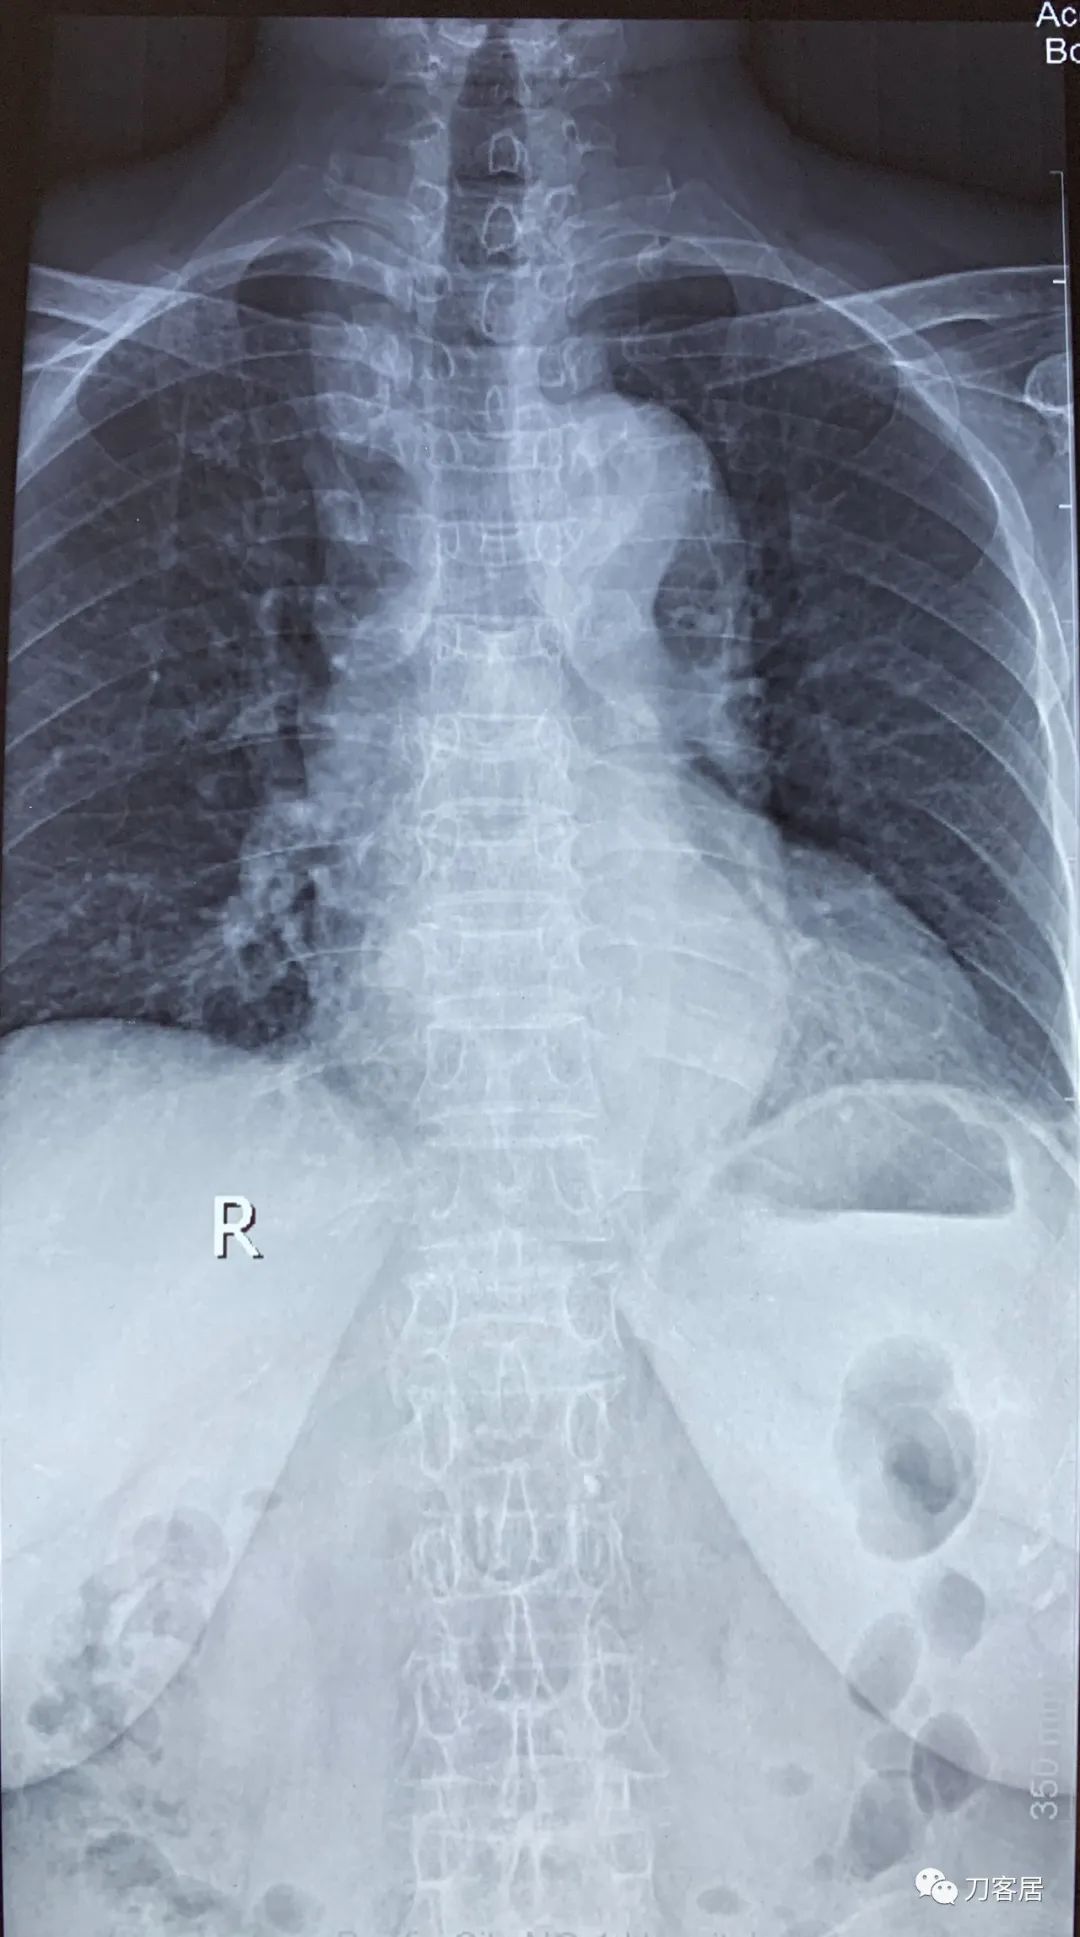

自带影像学资料提示胸椎,腰椎多发脊柱压缩性骨折。

诊断 : 重度骨质疏松症,胸椎、腰椎多发椎体压缩性骨折

图01-20200825胸椎正位X线片